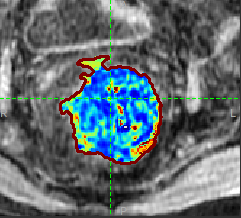

Manual ROI drawing and automated clustering methods for subregion analysis

ROI and subregion tools for:

Automatically generating data-driven subregions using supervoxels and K-means clustering.

Manually drawing ROIs on the images.

Calculating quantities and visualizing data within regions/ROIs.